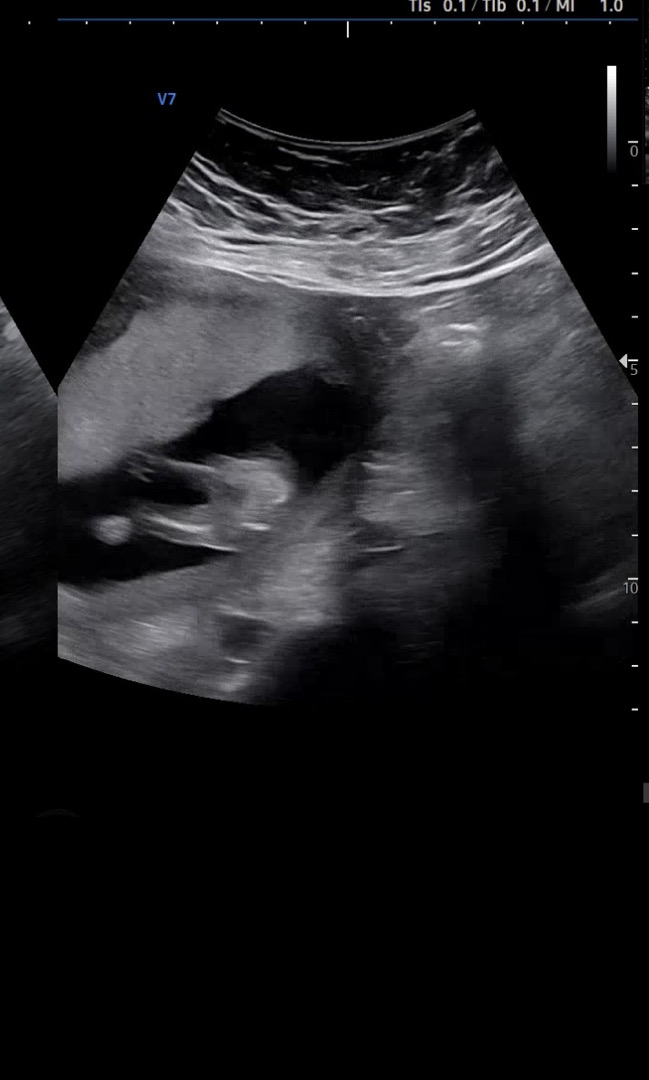

GPT는 남자라고 하는데 여러분의 생각은 어떠신가요? 오늘 병원 다녀왔고15주2일 차 입니다 정말 딸이 아닌 아들일까요?

그런데 오늘 저 주치 선생님은 애매하게 대답해주셨어요. 70% 딸일 것 같다고.

아들이면 바로 말 안해도 아시죠 이렇게 하셨는데 다음 번 진료에 1번 더 다시 보자고 그러시네요